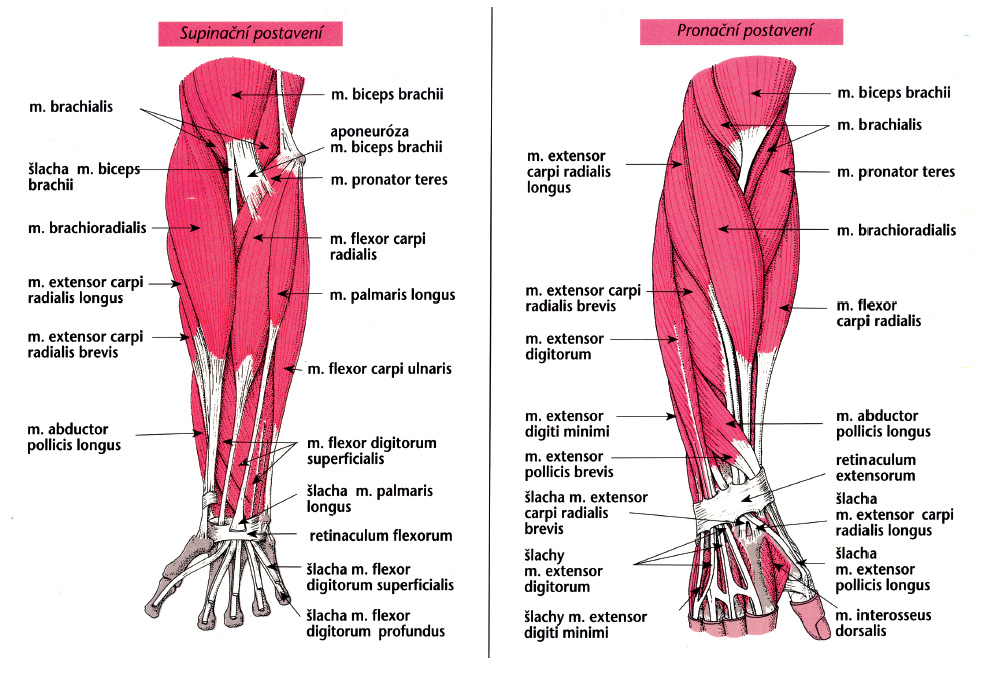

Анатомия мышцы Palmaris Longus